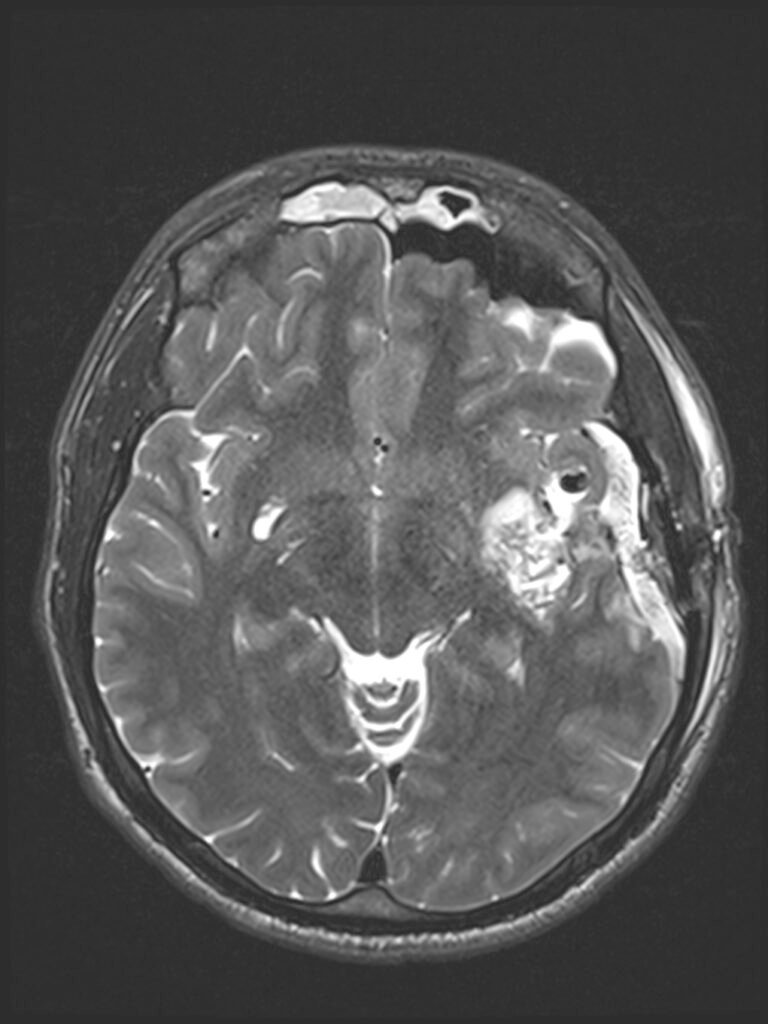

Tumora era bine delimitată, cu priză omogenă de contrast, și are origine din dura mater (foița externă a meningelui) de la nivelul șanțurilor olfactive – porțiunea din baza craniului pe unde trec nervii olfactivi. Aspectul RMN sugerează un diagnostic histopatologic de meningiom – tumoră benignă (în peste 95% din cazuri) .

Intervenția chirurgicală este cea mai bună soluție în asemenea situații, pentru că, deși benignă, tumora va continua să crească și va începe să determine și alte manifestări neurologice (crize comițiale, afectare vizuală, declin cognitiv – demență, etc.). De asemenea, cu cât tumor este mai mare, cu atât mai lungă și dificilă va fi operația, în timp ce pacientul va fi mai vârstnic și, posibil, cu mai multe suferințe cronice asociate. Un aspect care merită menționat este că portiunea posterioară a tumorii ajunge în apropierea celor doi nervi optici, fără a-i comprima (încă!).